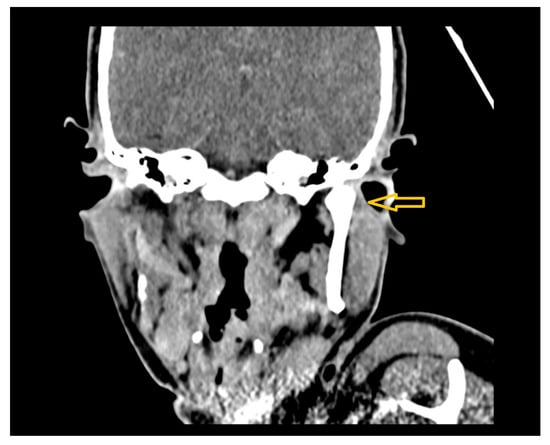

| 1 | Male | 48 | Osteoma of the coronoid process |

OPG CT | 19 mm | Coronoidectomy | 39 mm |